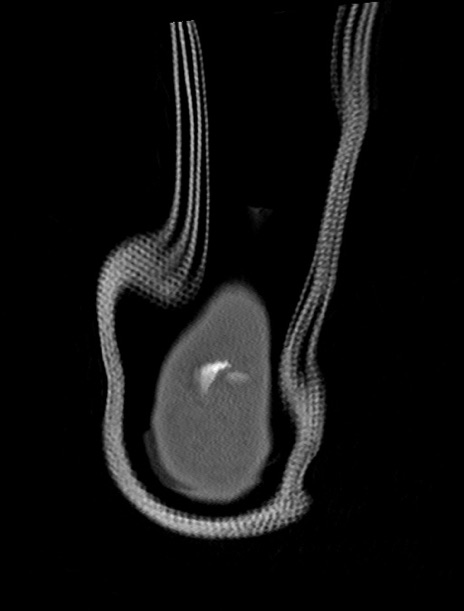

症例37 左足関節CT(冠状断像)

左足関節CT

3D再構成